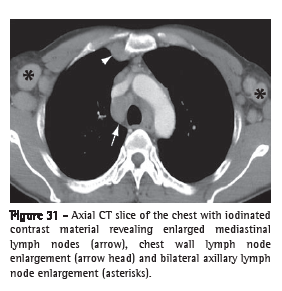

Air trapping (aprisionamento aéreo)

Air trapping is the retention of excess gas (air) in part of or all of the lung (especially upon exhalation), resulting from partial or total airway obstruction or secondary to focal abnormalities of lung compliance. It is recognized during the expiratory phase as reduced attenuation of the lung parenchyma, especially apparent as lower-than-usual density (Figure 1) and absence of volume reduction.(8-10)

See also Mosaic attenuation/perfusion pattern.